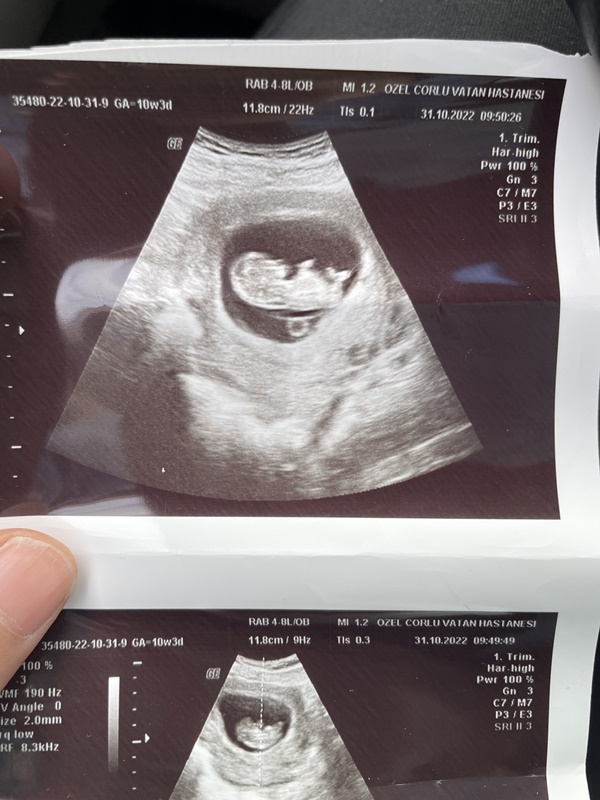

Merhabalar Bebeğimin Cinsiyetine bakar mısınız lütfen ramzi teorisi ya da nub teorisine göre cinsiyeti ne bebeğimin ?

Şimdi oldu hayatım. Umarım tahminim doğru çıkar. Bebeğin sağda olduğunu görüyorum yaptığım derinlemesine incelemeler ışığında KIZ olmaya çok yakın diyebilirim. 🙂

Yok yok sıkıntı değil iyiki birden çok resim atmışsın. Çok kötü olan resimleri zaten sildim. Cinsiyet için yeterli gördüğüm resim içinde KIZ olmaya çok yakın dedim bilgine tatlım. Biraz daha zaman geçince bir de NUB teorisine göre bakmak isterim.